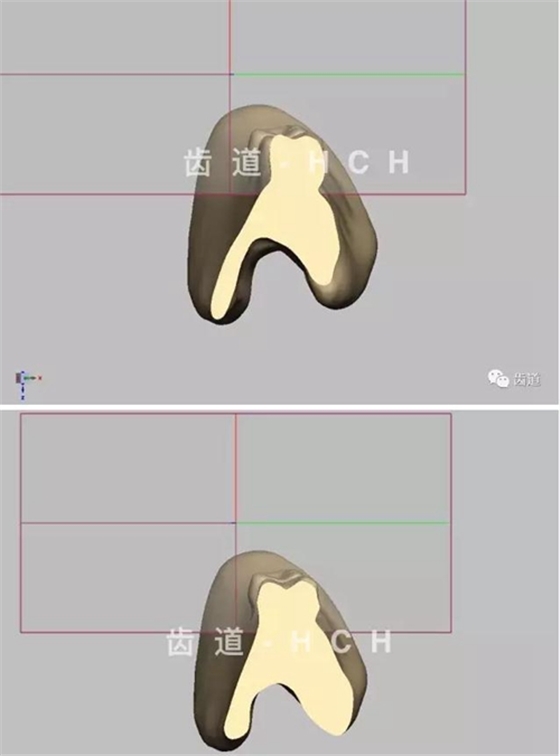

標(biāo)準(zhǔn)全口義齒模型截圖 科貿(mào)嘉友收錄